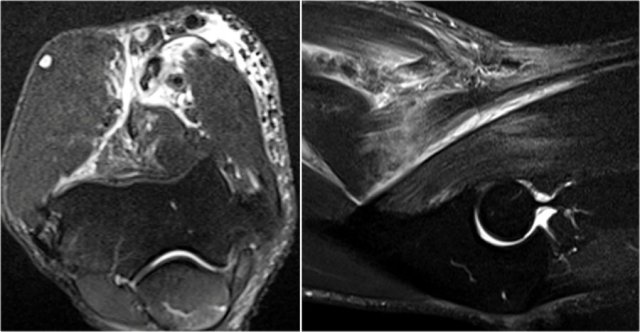

Here are sagittal and axial images of a patient who was referred to an orthopedic oncology surgeon for a mass near the elbow.

There is a partial tear (arrow) of the biceps tendon, but the question is, what is the structure that we are looking at and what is within it.

The structure is the radiobicipital bursa, so this is a bursitis.

Remember that the biceps tendon does not have a tendon sheaht, so tenosynovitis is not a possibility.

The differential diagnosis for the low intensity structures within the bursa is: synovial chondromatosis, PVNS and rice bodies.

It turned out to be rice bodies.

In any synovial lined joint or bursa these rice bodies can be formed as a result of chronic inflammation with synovial hypertrophy.

The villi will outgrow their blood supply, become necrotic and fall into the joint or bursa.

They are called rice bodies because when you open up the joint, they just look like rice.

Here another case.

The white arrow in the left sided image is pointing to the bursa.

Notice that the biceps is intact.

Next to the radiobicipital bursa (yellow arrow), also an interosseous bursa (red arrow) was described by Abdalla Skaf in Radiology in the article entitled: Bicipitoradial Bursitis: MR Imaging Findings.

Sometimes these masses mimic a tumor or they can cause impingement on the radial nerve when they become very large.